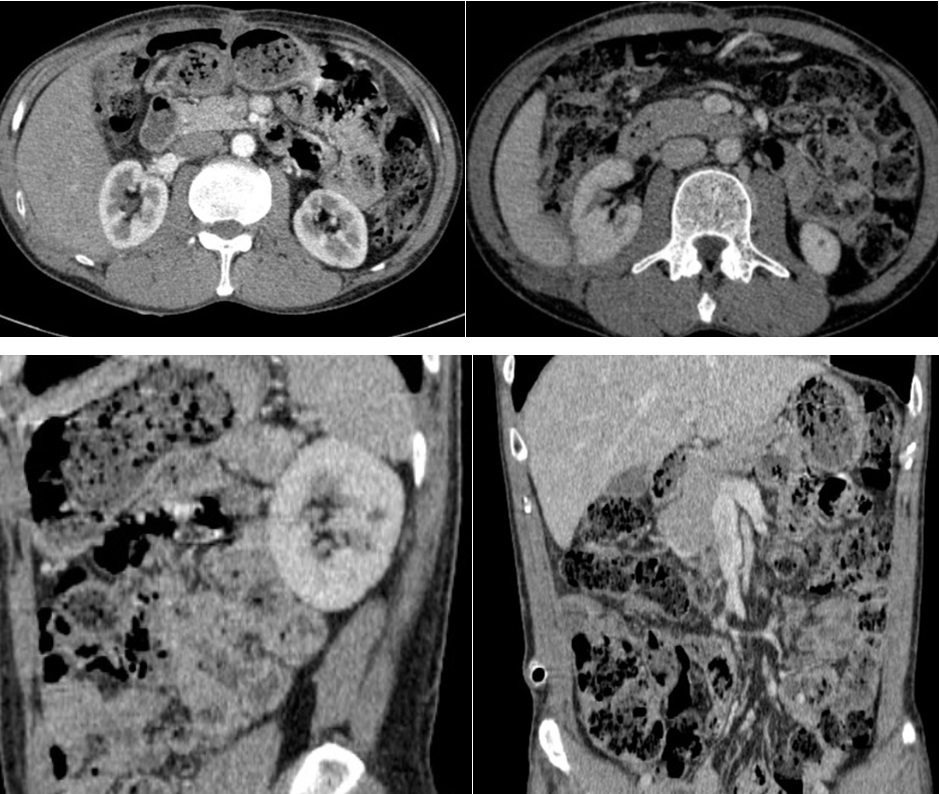

– Hình ảnh chụp cắt lớp vi tính ổ bụng (4/2025): Hình ảnh sau mổ u sau phúc mạc bên phải, hiện thấy tụ ít dịch mỏng, đám thâm nhiễm khoang sau phúc mạc. Ít dịch ổ bụng vùng hạ vị.

Hình 4. Hình ảnh chụp cắt lớp vi tính ổ bụng: sau mổ u sau phúc mạc bên phải, hiện thấy tụ ít dịch mỏng, đám thâm nhiễm khoang sau phúc mạc (sau mổ 1 tháng)